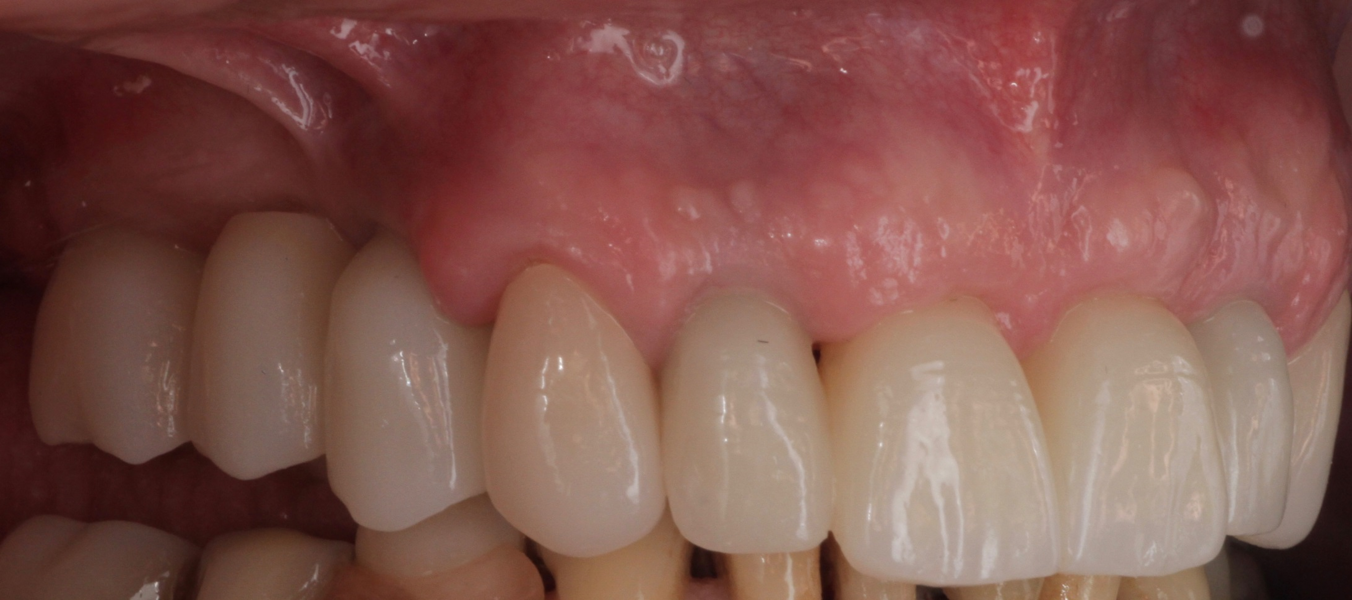

Definitive prosthetic treatment was performed after completion of implant healing with three CAD/CAM-fabricated monolithic zirconia bridges (DD cubeX2, Dental Direkt). The bridges were screwed on to BEGO titanium base abutments (Figs. 14–16). Good fit of the prosthetic superstructures was displayed in the radiograph after placement (Fig. 17). The two-year follow-up examination in July 2019 revealed excellent aesthetic and clinical soft-tissue conditions (Figs. 18–20). No radiographic bone loss had occurred at the implant sites (Fig. 21). Neither the submerged central incisors nor the distobuccal molar root displayed any signs of periapical inflammation, and the patient reported no complications. The patient’s oral hygiene had improved significantly during the follow-up period.

Fig. 19: Right lateral aspect of the restorations after the two-year follow-up period

Fig. 20: Left lateral aspect of the restorations after the two-year follow-up period.